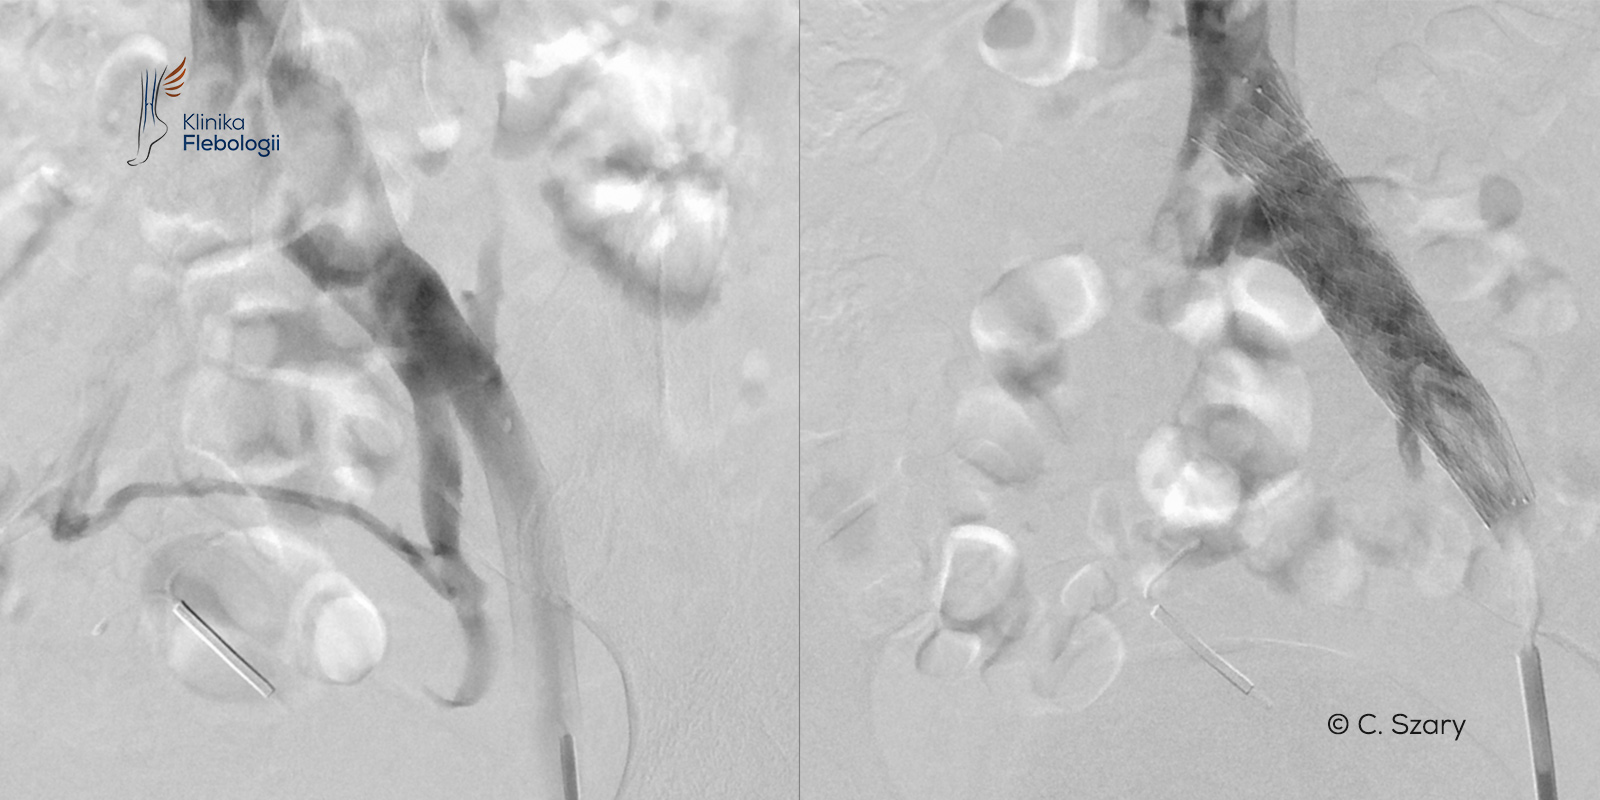

Zjawisko May-Thurnera po raz pierwszy dokładnie opisane zostało w roku 1965. Współcześnie definiowane jest ono jako utrudnienie odpływu krwi żylnej z poziomu kończyny dolnej lewej powstałe wskutek obecności zmian o typie przegrody (przegród) w świetle lewej żyły biodrowej wspólnej lewej lub z powodu jej ucisku, wywołanego przez przebiegającą w bezpośredniej bliskości tętnicę biodrową wspólną prawą.

Ucisk lewej żyły biodrowej wspólnej na poziomie jej skrzyżowania z prawą tętnicą biodrową wspólną i niekorzystne konsekwencje z tego wynikającego, to jedno z ważniejszych zjawisk anatomicznych w układzie żylnym, doprowadzające do wczesnej niewydolności żylnej miednicy, niewydolności żylnej kończyn dolnych (częściej lewej), a także groźnej dla życia zakrzepicy proksymalnej w lewej kończynie dolnej.

Obecnie w erze daleko rozwiniętej diagnostyki obrazowej (flebografia cyfrowa, ultrasonografia wewnątrznaczyniowa IVUS), a także dzięki współczesnym technikom radiologii interwencyjnej, stosuje się leczenie wewnątrznaczyniowe lub wewnątrznaczyniowe połączone z chirurgią małoinwazyjną (tzw. postępowanie hybrydowe).

Dokładne zdiagnozowanie zjawiska, określenie stopnia ucisku pnia żylnego oraz konfiguracji wszystkich naczyń żylnych i tętniczych, pozwalają na zastosowanie wewnątrznaczyniowego leczenia celowanego. Terapia żylnych zespołów uciskowych polega na wyleczeniu przyczyny (np. wystentowaniu zwężonego naczynia żylnego) i w dalszej kolejności na eliminacji skutków choroby, tj. najczęściej zamknięciu powstałych wcześniej żylaków (np. przy użyciu technik embolizacyjnych).